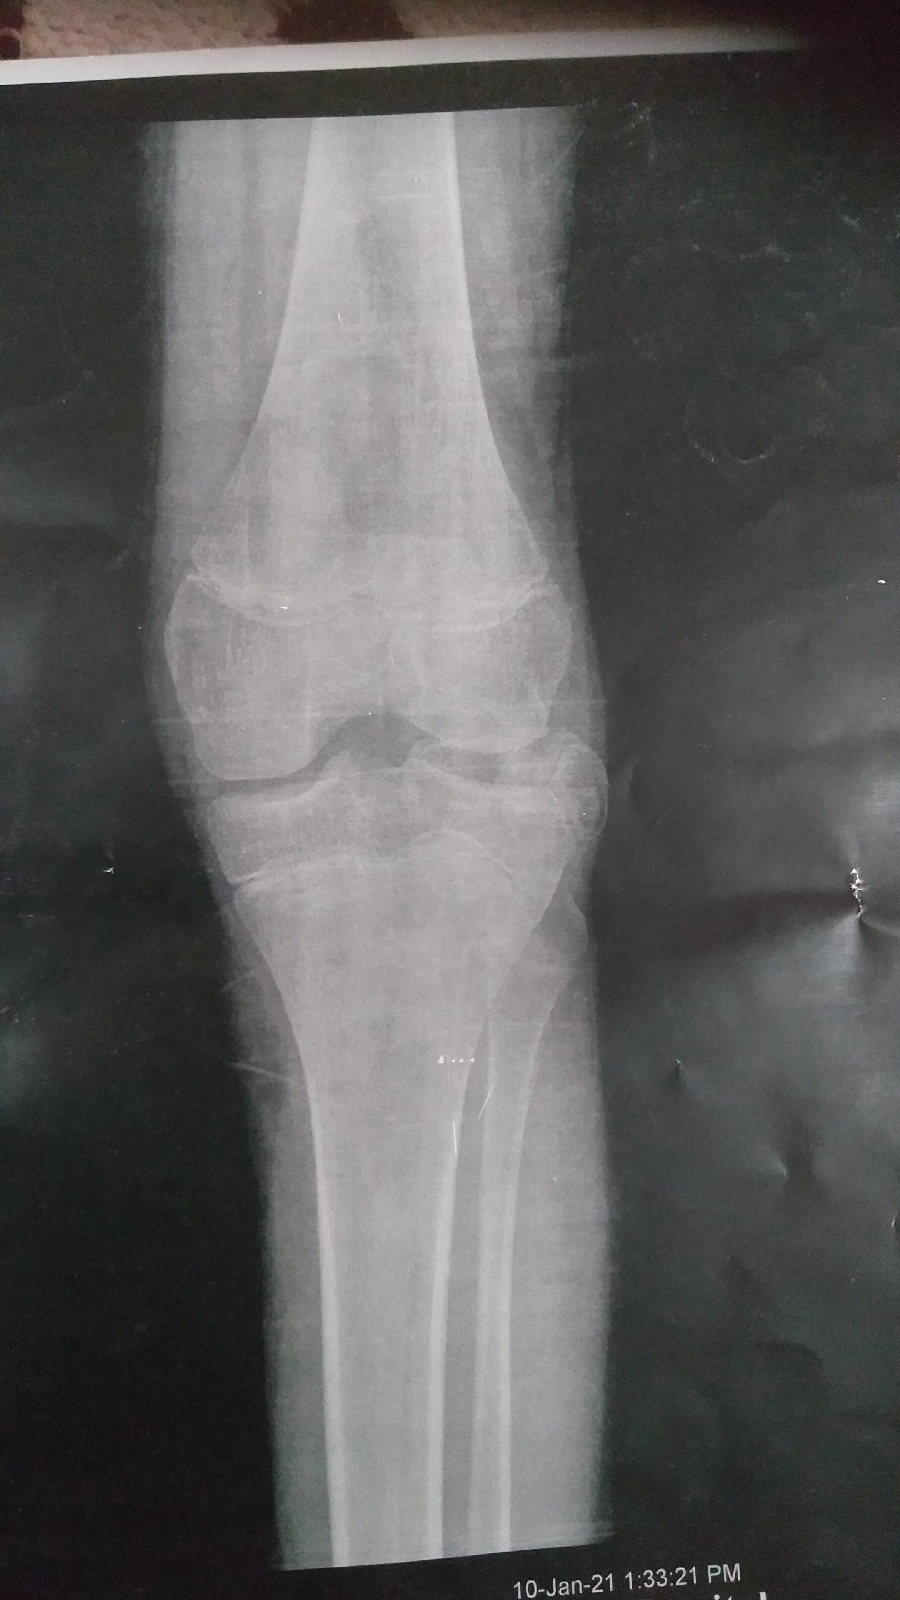

Quiz!! A case of well defined calcified knee mass.

I share with you a 19 years old case of intra articular mass which is well defined on X ray and Painful. He has flexion deformity of the knee and moderate effusion. His symptoms started 6 months ago.

What is your diagnosis and management?? Leave your comment below.

I will share with you MRI after some days.